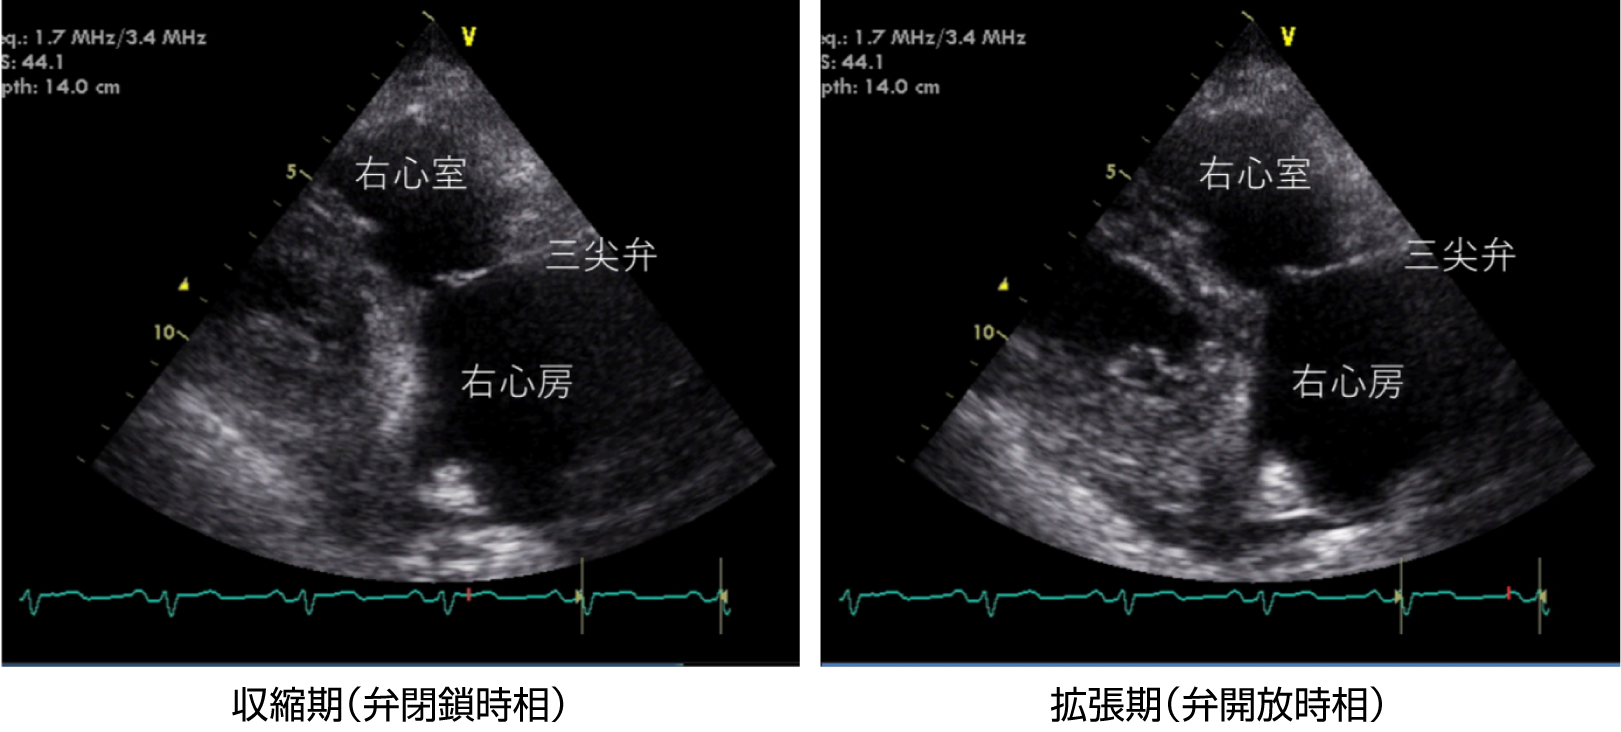

図2 三尖弁狭窄症の心エコー図(右室流入断面)

三尖弁は肥厚し可動制限があり、拡張期にも開放が不十分である(弁口面積が減少)。